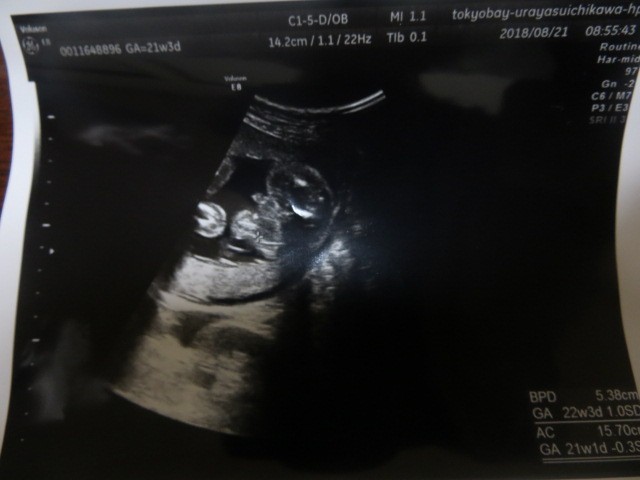

妊娠6ヶ月(21週3日)撮影日:2018年8月21日

横顔

動かない

横顔から

少し動く